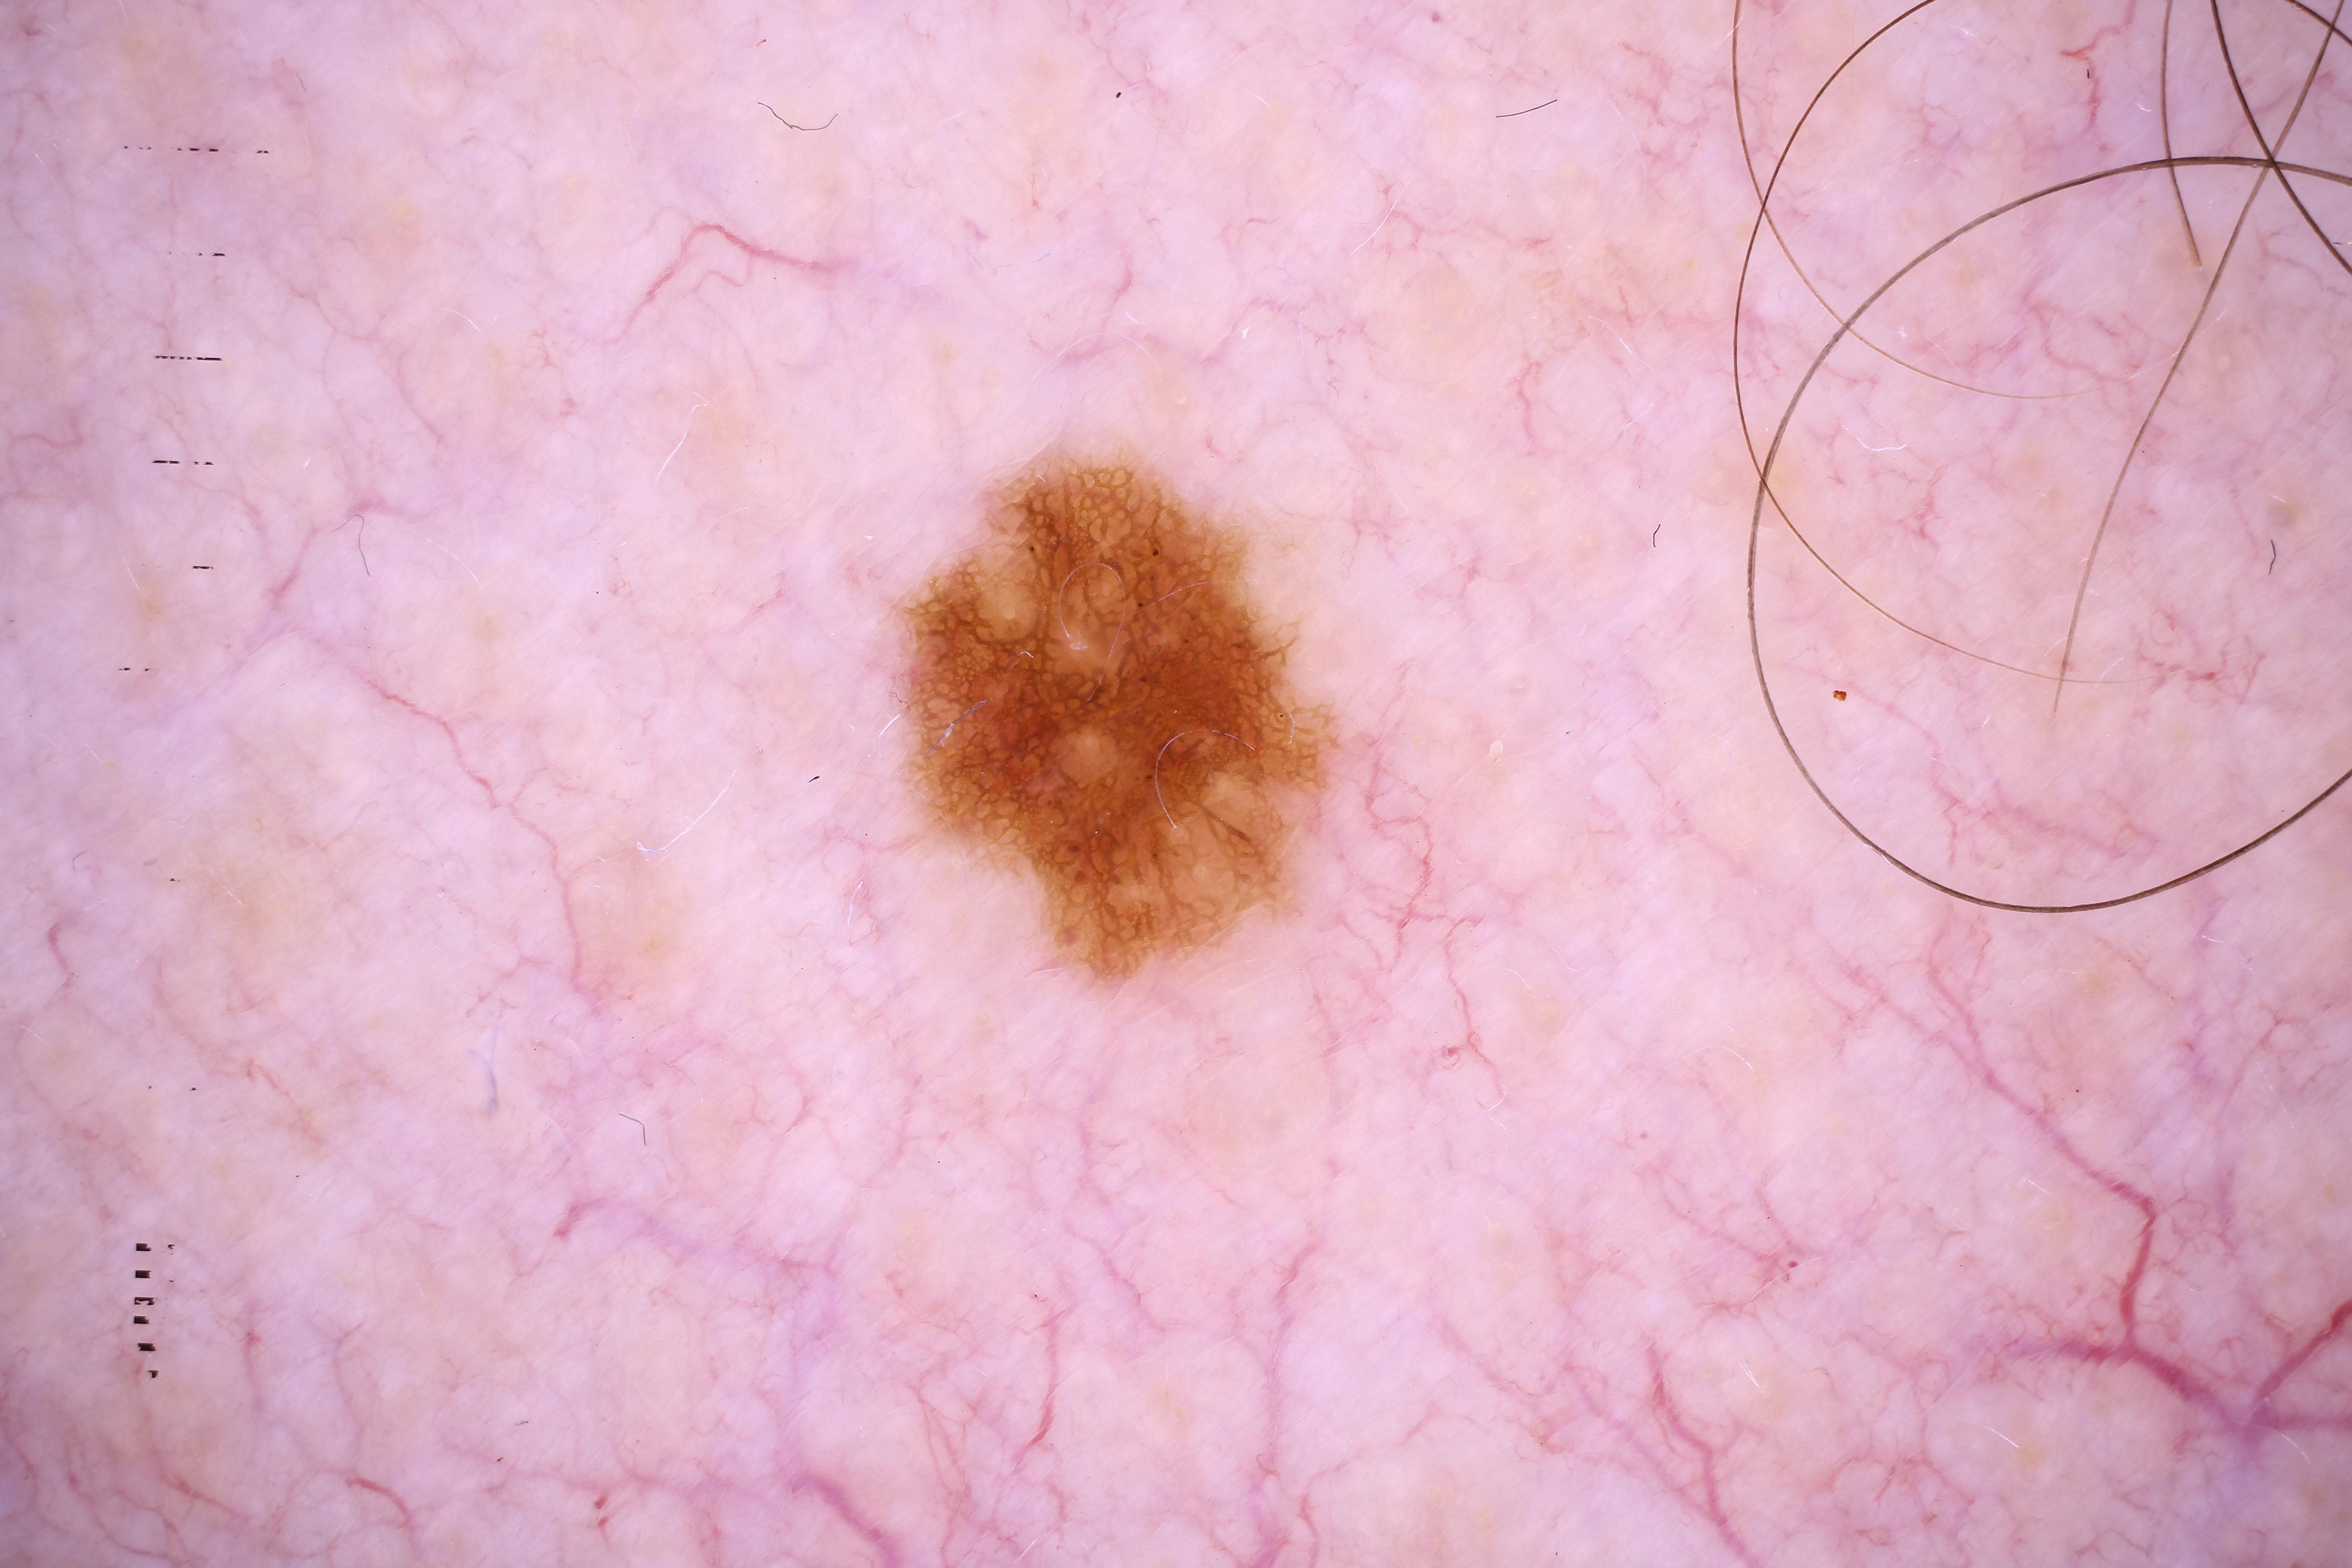

{

"acquisition_day": 187,

"age_approx": 60,

"anatom_site_general": "posterior torso",

"concomitant_biopsy": true,

"dermoscopic_type": "contact non-polarized",

"diagnosis_1": "Benign",

"diagnosis_2": "Benign melanocytic proliferations",

"diagnosis_3": "Nevus",

"diagnosis_4": "Nevus, NOS, Compound",

"diagnosis_confirm_type": "histopathology",

"image_type": "dermoscopic",

"lesion_id": "IL_9050924",

"patient_id": "IP_8191902",

"personal_hx_mm": true,

"sex": "male"

}